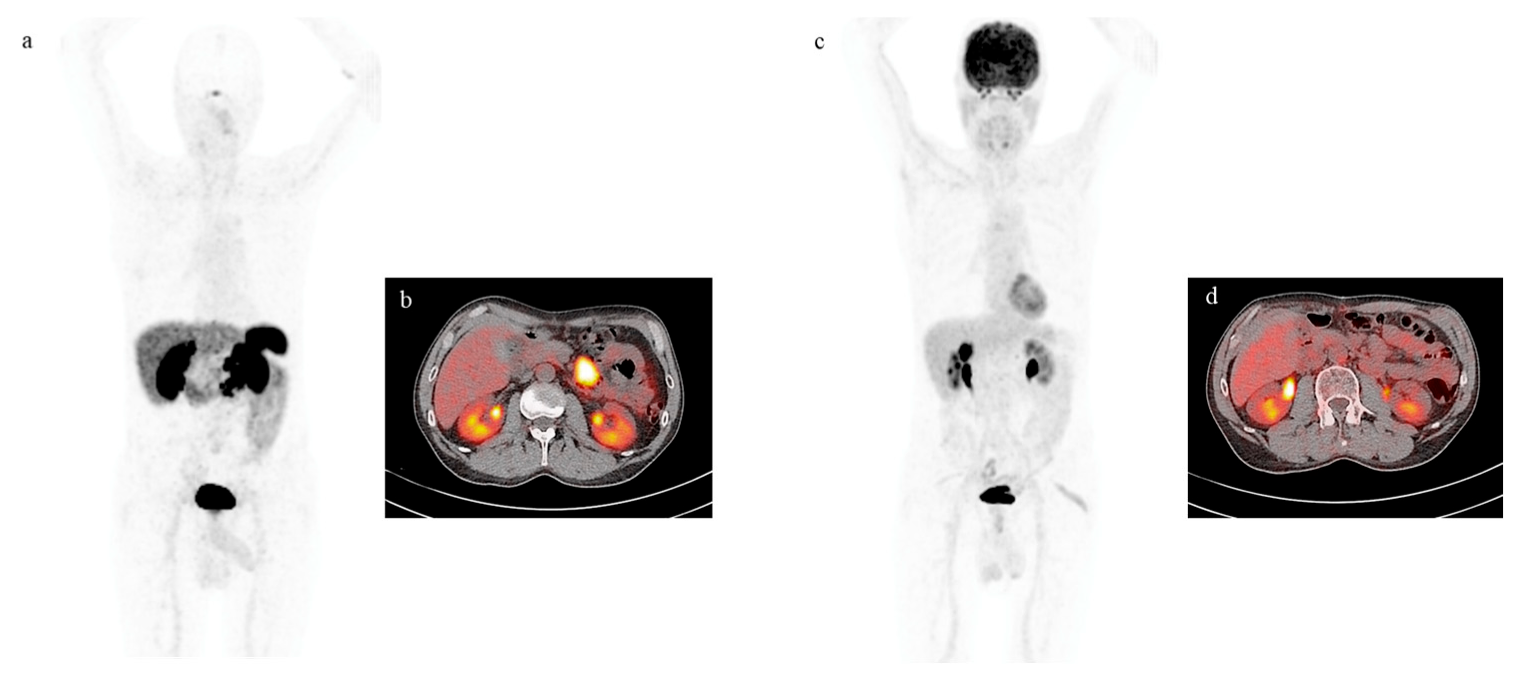

4. Functional Imaging by SST Analogs

5. Imaging Analysis